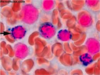

Which abnormality is shown in this pic? What are its possible causes?

Traumatic Hemolysis

Note the schistocytes, burr cells, helmet cells

Possible Causes: DIC, long distance running, prosthetic heart valves, TTP